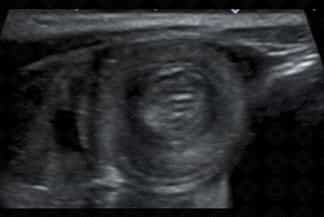

Texto alternativo para a imagem Figura 2. Créditos: Dra. Elazir Mota - Rio de Janeiro/RJ

Descrição das figura 2, 3 e 4: Ultrassonografia do abdome evidenciando o "sinal do alvo" - múltiplos anéis ecogênicos e concêntricos alternando-se com regiões hipoecoicas (os múltiplos anéis ecogênicos, na realidade, representam interfaces da parede intestinal), localizado na fossa ilíaca direita, caracterizando um quadro de invaginação intestinal ileocólica.

Exame de imagem: Por se tratar de patologia pediátrica, diante dessa suspeita diagnóstica, deve ser solicitada ultrassonografia (USG) de abdome que diagnostica quase a totalidade dos casos quando realizada por médico experiente (sua sensibilidade varia entre 95-100%, com especificidade de 88-100%). A invaginação aparece na USG como "massa" complexa e com anéis concêntricos hipo e hiperecoicos que se alternam (o sinal da rosquinha ou do alvo ). Nas imagens em eixo longo, a intussuscepção lembra um rim no qual o "córtex renal" representa a intussuscepção edematosa hipoecoica e o "seio renal" corresponde à gordura mesentérica invaginada (sinal do pseudorrim ).